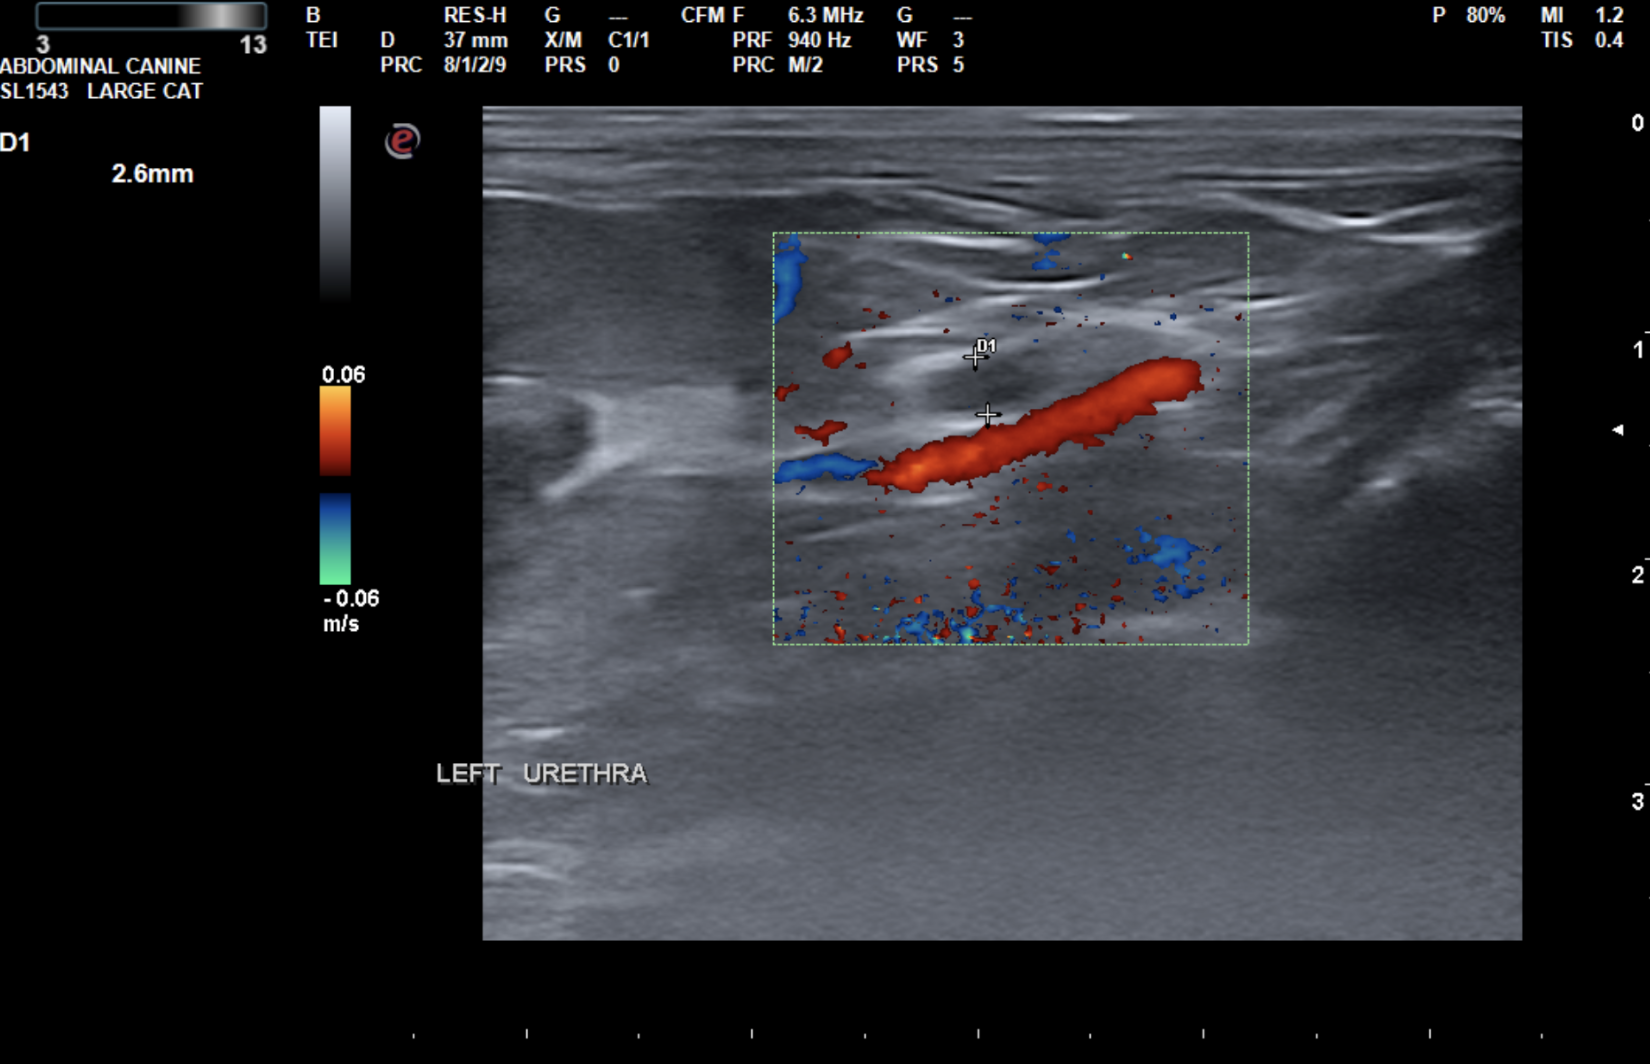

The left ureter was mildly dilated from the kidney to the papilla (up to 2.6mm). There was a severely hyperechoic, minimally shadowing, rounded structure in the left papilla (1.7x1.8mm). The bladder was moderately distended with anechoic urine and of normal contour and thickness. No neoplasia or other uroliths were noted.

Image 2: Left ureter just distal to kidney

Image 3- Left Ureter approaching the bladder